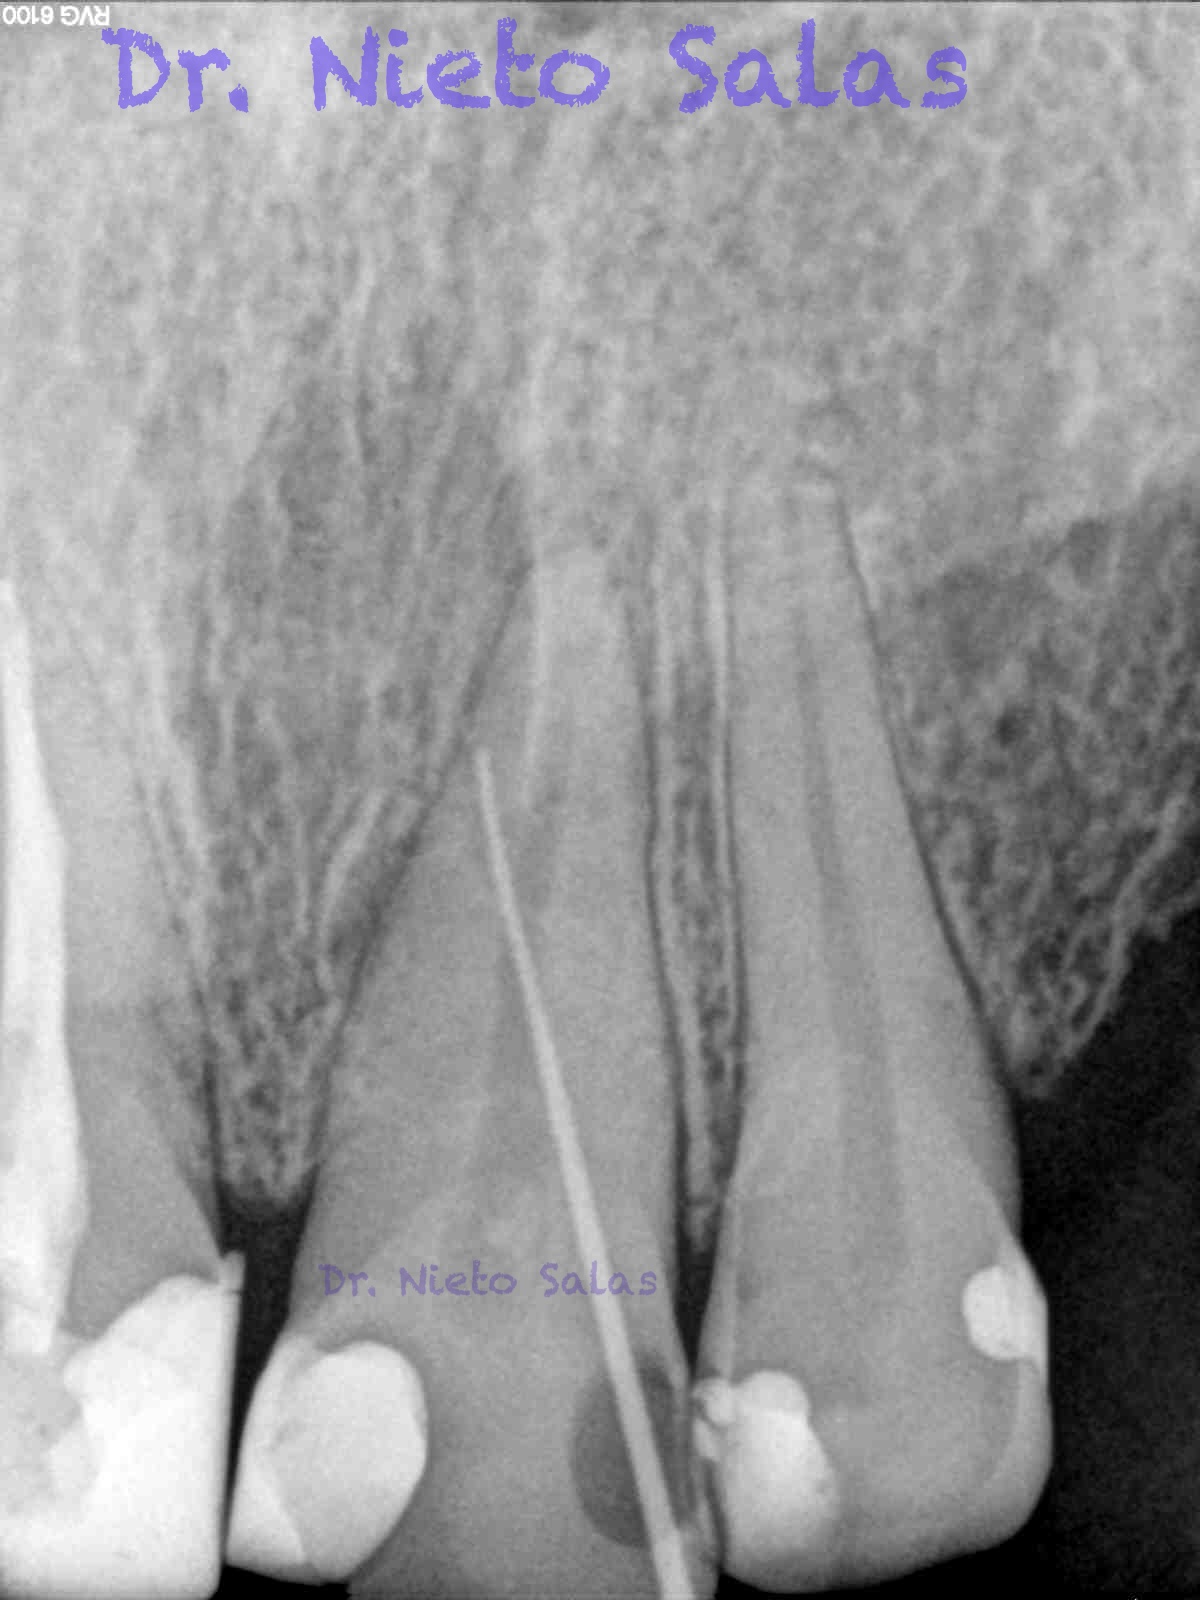

Pero no todo se va a dejar al «poder de la irrigación»,  es muy importante la biomecánica, y la intuición para poder instrumentar esos pequeños conductos laterales que es muchas ocasiones nos dan problemas. Así, pues, os pongo un par de casos que con ayuda de esta «intuición» pudimos hacer un buen tratamiento.

Presentaban un sondaje normal, y sospechamos de que podía tratarse de lesiones por conductos laterales.

Una vez que hemos desbridado biomecánicamente con limas de muy pequeño diámetro, obturamos:

Como sabrás, son muchas las piezas dentarias que presentan conductos laterales, lo primero, es descartar que la imagen pueda ser una fractura vertical, después conformo el sistema de conductos, y si sospecho de un conducto lateral ( INTUICIÓN ) precurvo una lima de pequeño diámetro y exploro las paredes en la zona de puede estar. En ocasiones, puedes ver un pequeño puntito, la entrada, con el microscopio. (es raro).